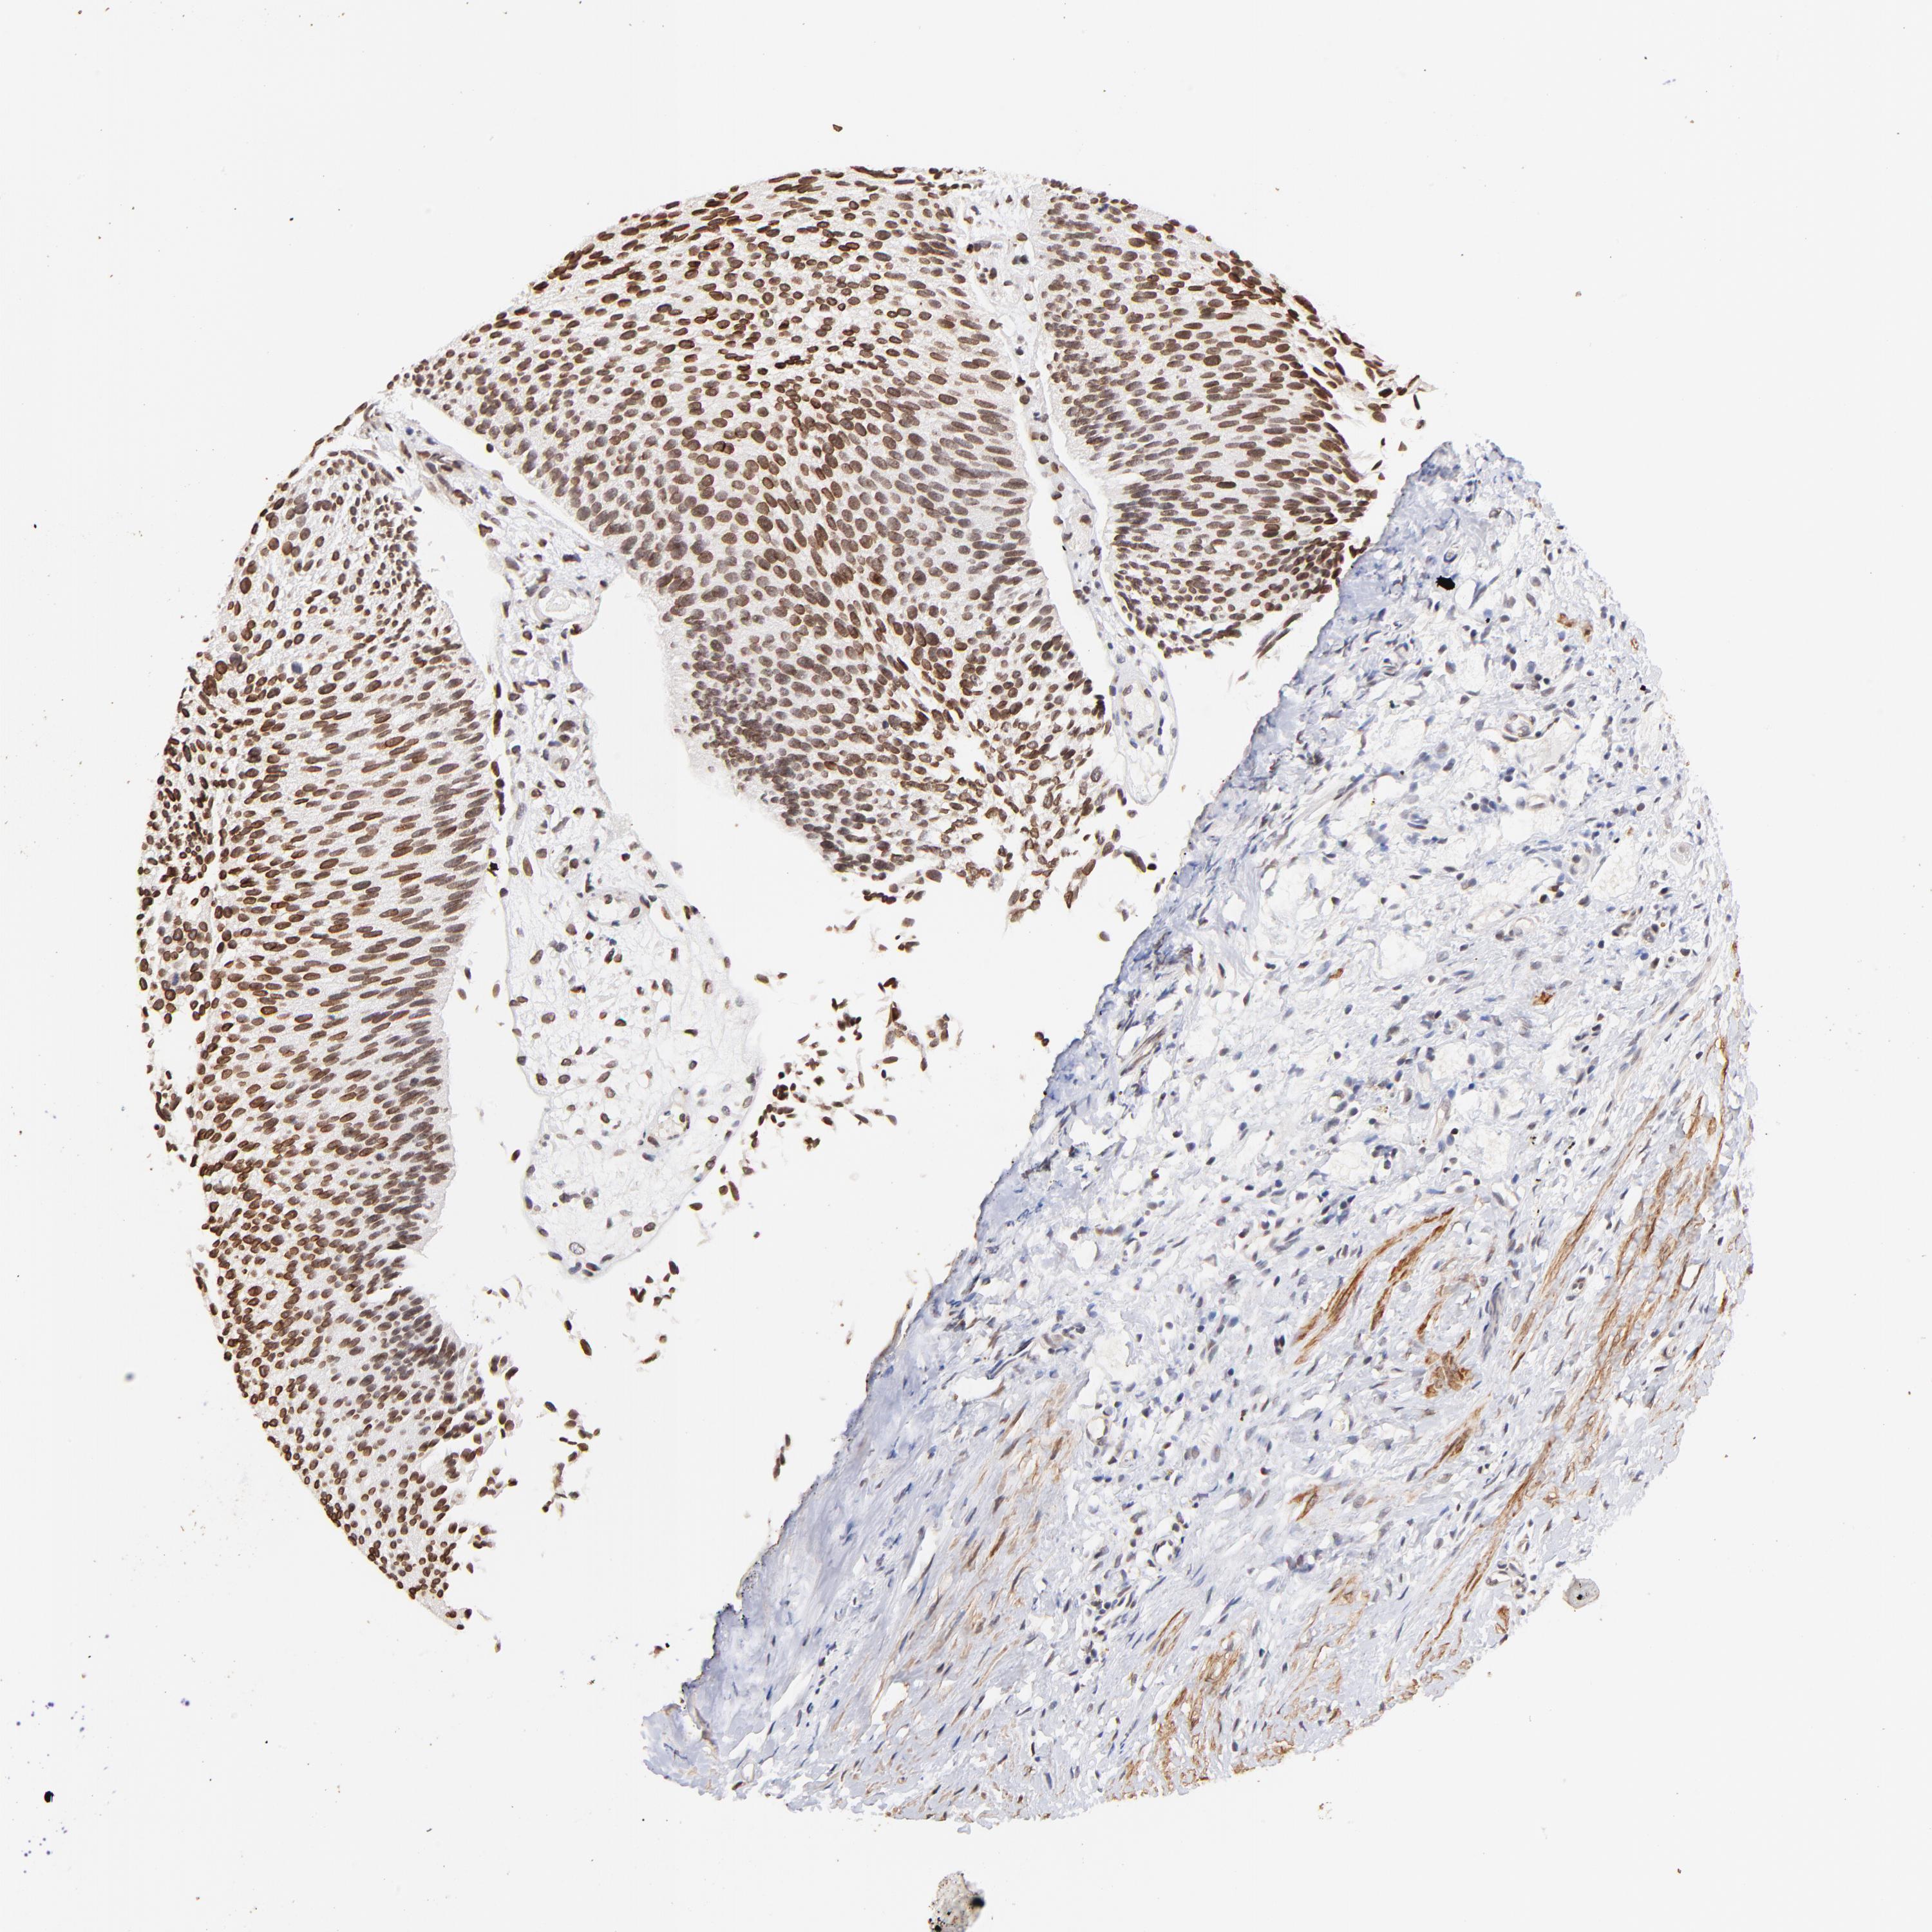

UROTHELIAL CANCER - Protein expressioni

A mouse-over function shows sample information and annotation data. Click on an image to view it in a full screen mode. Samples can be filtered based on level of antibody staining by selecting one or several of the following categories: high, medium, low and not detected. The assay and annotation is described here.

Note that samples used for immunohistochemistry by the Human Protein Atlas do not correspond to samples in the TCGA dataset.

Antibody stainingi

Antibody staining in the annotated cell types in the current human tissue is reported as not detected, low, medium, or high, based on conventional immunohistochemistry profiling in selected tissues. This score is based on the combination of the staining intensity and fraction of stained cells.

Each image is clickable and will lead to virtual microscopy that enables deeper exploration of all samples and also displays staining intensity scores, fraction scores and subcellular localization as well as patient and tissue information for each sample.

Antibody HPA003030

Staining

High

Medium

Low

Not detected

Intensity

Strong

Moderate

Weak

Negative

Quantity

>75%

75%-25%

<25%

None

Location

Nuclear

Cytoplasmic/membranous

Cytoplasmic/membranous,nuclear

Urothelial carcinoma, High grade

Urothelial carcinoma, Low grade

Adenocarcinoma, NOS